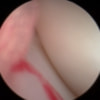

関節鏡検査を実施いたしました。関節鏡検査では、重度の滑膜炎および前十字靭帯の完全断裂が認められました。半月板に損傷は認められませんでした。

関節穿刺を行い、好中球はなく、少数のマクロファージや滑膜細胞が認められるました。膝蓋骨脱臼および前十字靭帯断裂による退行性の関節炎を疑い、関節鏡検査を実施いたしました。関節鏡検査では、重度の滑膜炎および前十字靭帯の完全断裂が認められました。内外側とも半月板に損傷は認められませんでした。